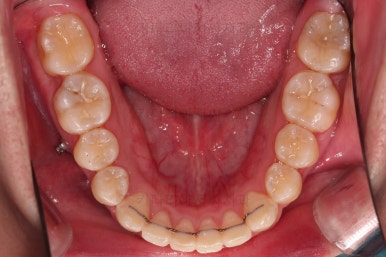

우선 브라켓을 부착했고요.

이번에 환자분이 선택하신 장치는 엠파워 메탈이라고 하는 자가결찰 금속장치인데요.

미니스크류가 식립되었고요.

결손치아도 오른쪽, 부정교합도 오른쪽이어서 오른쪽 위아래 각 1개씩 식립이 되었어요.

물론 윗니는 앞으로 당기는 용도, 아랫니는 뒤로 미는 용도였습니다.